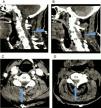

In traumatic brain injury (TBI), an abrupt extension–flexion movement could have caused the rupture of subarachnoid vessels. This, accompanied by the slowed blood “wash out” (probably due to the previous osteoarthrosis and spinal canal stenosis), led to the formation of an organized clot, which caused an acute spinal cord compression syndrome.

Cervical subarachnoid spinal hematoma can present as Brown-Séquard syndrome. The treatment is prompt surgical removal and decompression. The posterior approach (partial hemilaminectomy with or without laminoplasty) with microsurgical technique is feasible, fast and simple to evacuate the hematoma with good results. Surgical nuances in posterior approach are: small spinal canal, difficulty in mobilizing the cervical cord, these haematomas are wrapped and attached to the spinal cord or nerve roots by multiple arachnoid bands, requiring techniques of Microdissection for its evacuation unlike the epidural and subdural haematomas that are easily aspirated.